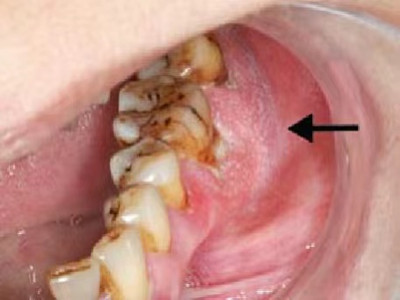

牙龈癌多源于牙间乳头及龈缘区,溃疡呈表浅、淡红,以后可出现增生。由于黏骨膜与牙槽突附着甚紧,较易早期侵犯牙槽突骨膜及骨质,进而出现牙松动,并可发生脱落。X线片可出现恶性肿瘤的破坏特征虫蚀状不规则吸收。

牙龈癌常发生继发感染,肿瘤伴以坏死组织,触之易出血。体积过大时可出现面部肿胀,浸润皮肤。